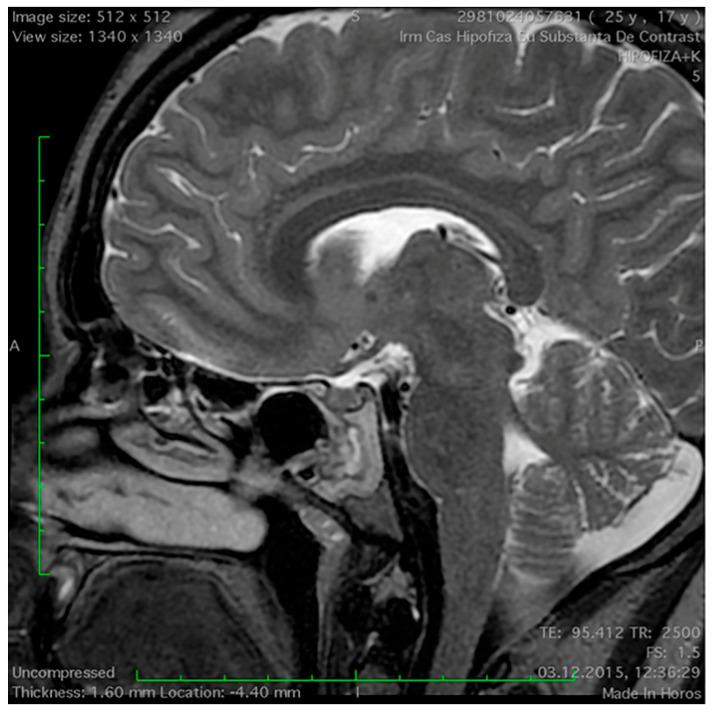

蝶窦在无功能垂体腺瘤患者中的磁共振成像特征。

Magnetic Resonance Imaging Features of the Sphenoid Sinus in Patients with Non-Functioning Pituitary Adenoma.

: A magnetic resonance imaging (MRI) scan is part of the diagnostic protocol in pituitary adenoma patients. The goal of the present study is to present and analyse the MRI appearances of the sphenoid sinus (SS) in patients with non-functioning pituitary adenoma (NFPA). : This is a retrospective case-control study conducted between January 2015 and December 2023 in a tertiary referral hospital. Forty NFPA patients were included in the study group, while the control group consisted of 30 age- and gender-matched cases. : The sellar type of SS pneumatization was the most frequently encountered pattern among both groups. The presence of the lateral recess of the SS, mucosal cysts, and sphenoethmoidal cells was similar in both patient groups. The proportion of patients with SS mucosal thickness greater than 3 mm was 42.5% in NFPA group and 3% in the control group, and this difference was statistically significant ( < 0.001). The space between the two optic nerves was significantly larger in the NFPA group as compared to the control group ( < 0.001). : Our study was able to establish a statistically significant association between the presence of NFPA and both the thickening of the SS mucosa and increased space between optic nerves.

摘要

磁共振成像(MRI)扫描是垂体腺瘤患者诊断方案的一部分。本研究的目的是展示和分析无功能垂体腺瘤(NFPA)患者蝶窦(SS)的 MRI 表现。

这是一项回顾性病例对照研究,于 2015 年 1 月至 2023 年 12 月在一家三级转诊医院进行。研究组纳入了 40 例 NFPA 患者,对照组包括 30 例年龄和性别匹配的病例。

两组中最常见的蝶窦气化类型是鞍型。两组患者的蝶窦外侧隐窝、黏膜囊肿和蝶筛窦细胞均相似。NFPA 组中 SS 黏膜厚度大于 3 毫米的患者比例为 42.5%,而对照组为 3%,差异具有统计学意义(<0.001)。与对照组相比,NFPA 组视神经之间的空间明显更大(<0.001)。

我们的研究能够确定 NFPA 的存在与 SS 黏膜增厚和视神经之间空间增大之间存在统计学显著关联。